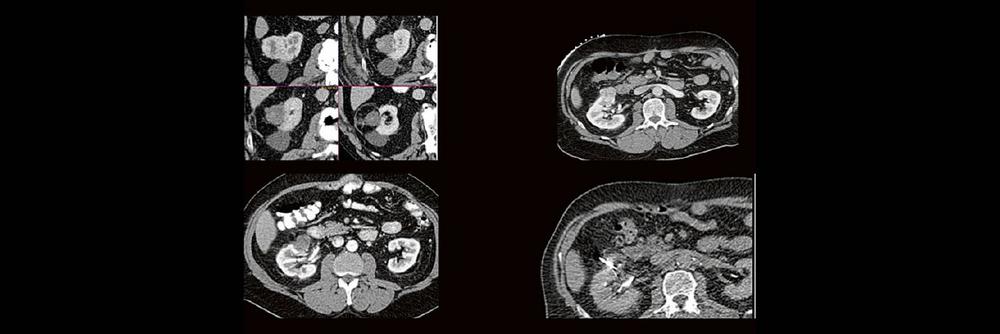

Back to the roots! Gute Kenntnisse der Anatomie sind der Schlüssel zur guten Planung, Durchführung und richtigen Diagnosestellung im CT des Abdomens. Lernen sie unverkrampft

- schnelle Orientierungspunkte für den Alltagsgebrauch

- richtiges Kontrastmittel-Timing im Bild erkennen

- Anatomie in Pathologie übersetzen

Haben Sie es erkannt? Probieren Sie selbst im lockeren Fallquiz zum mitraten.